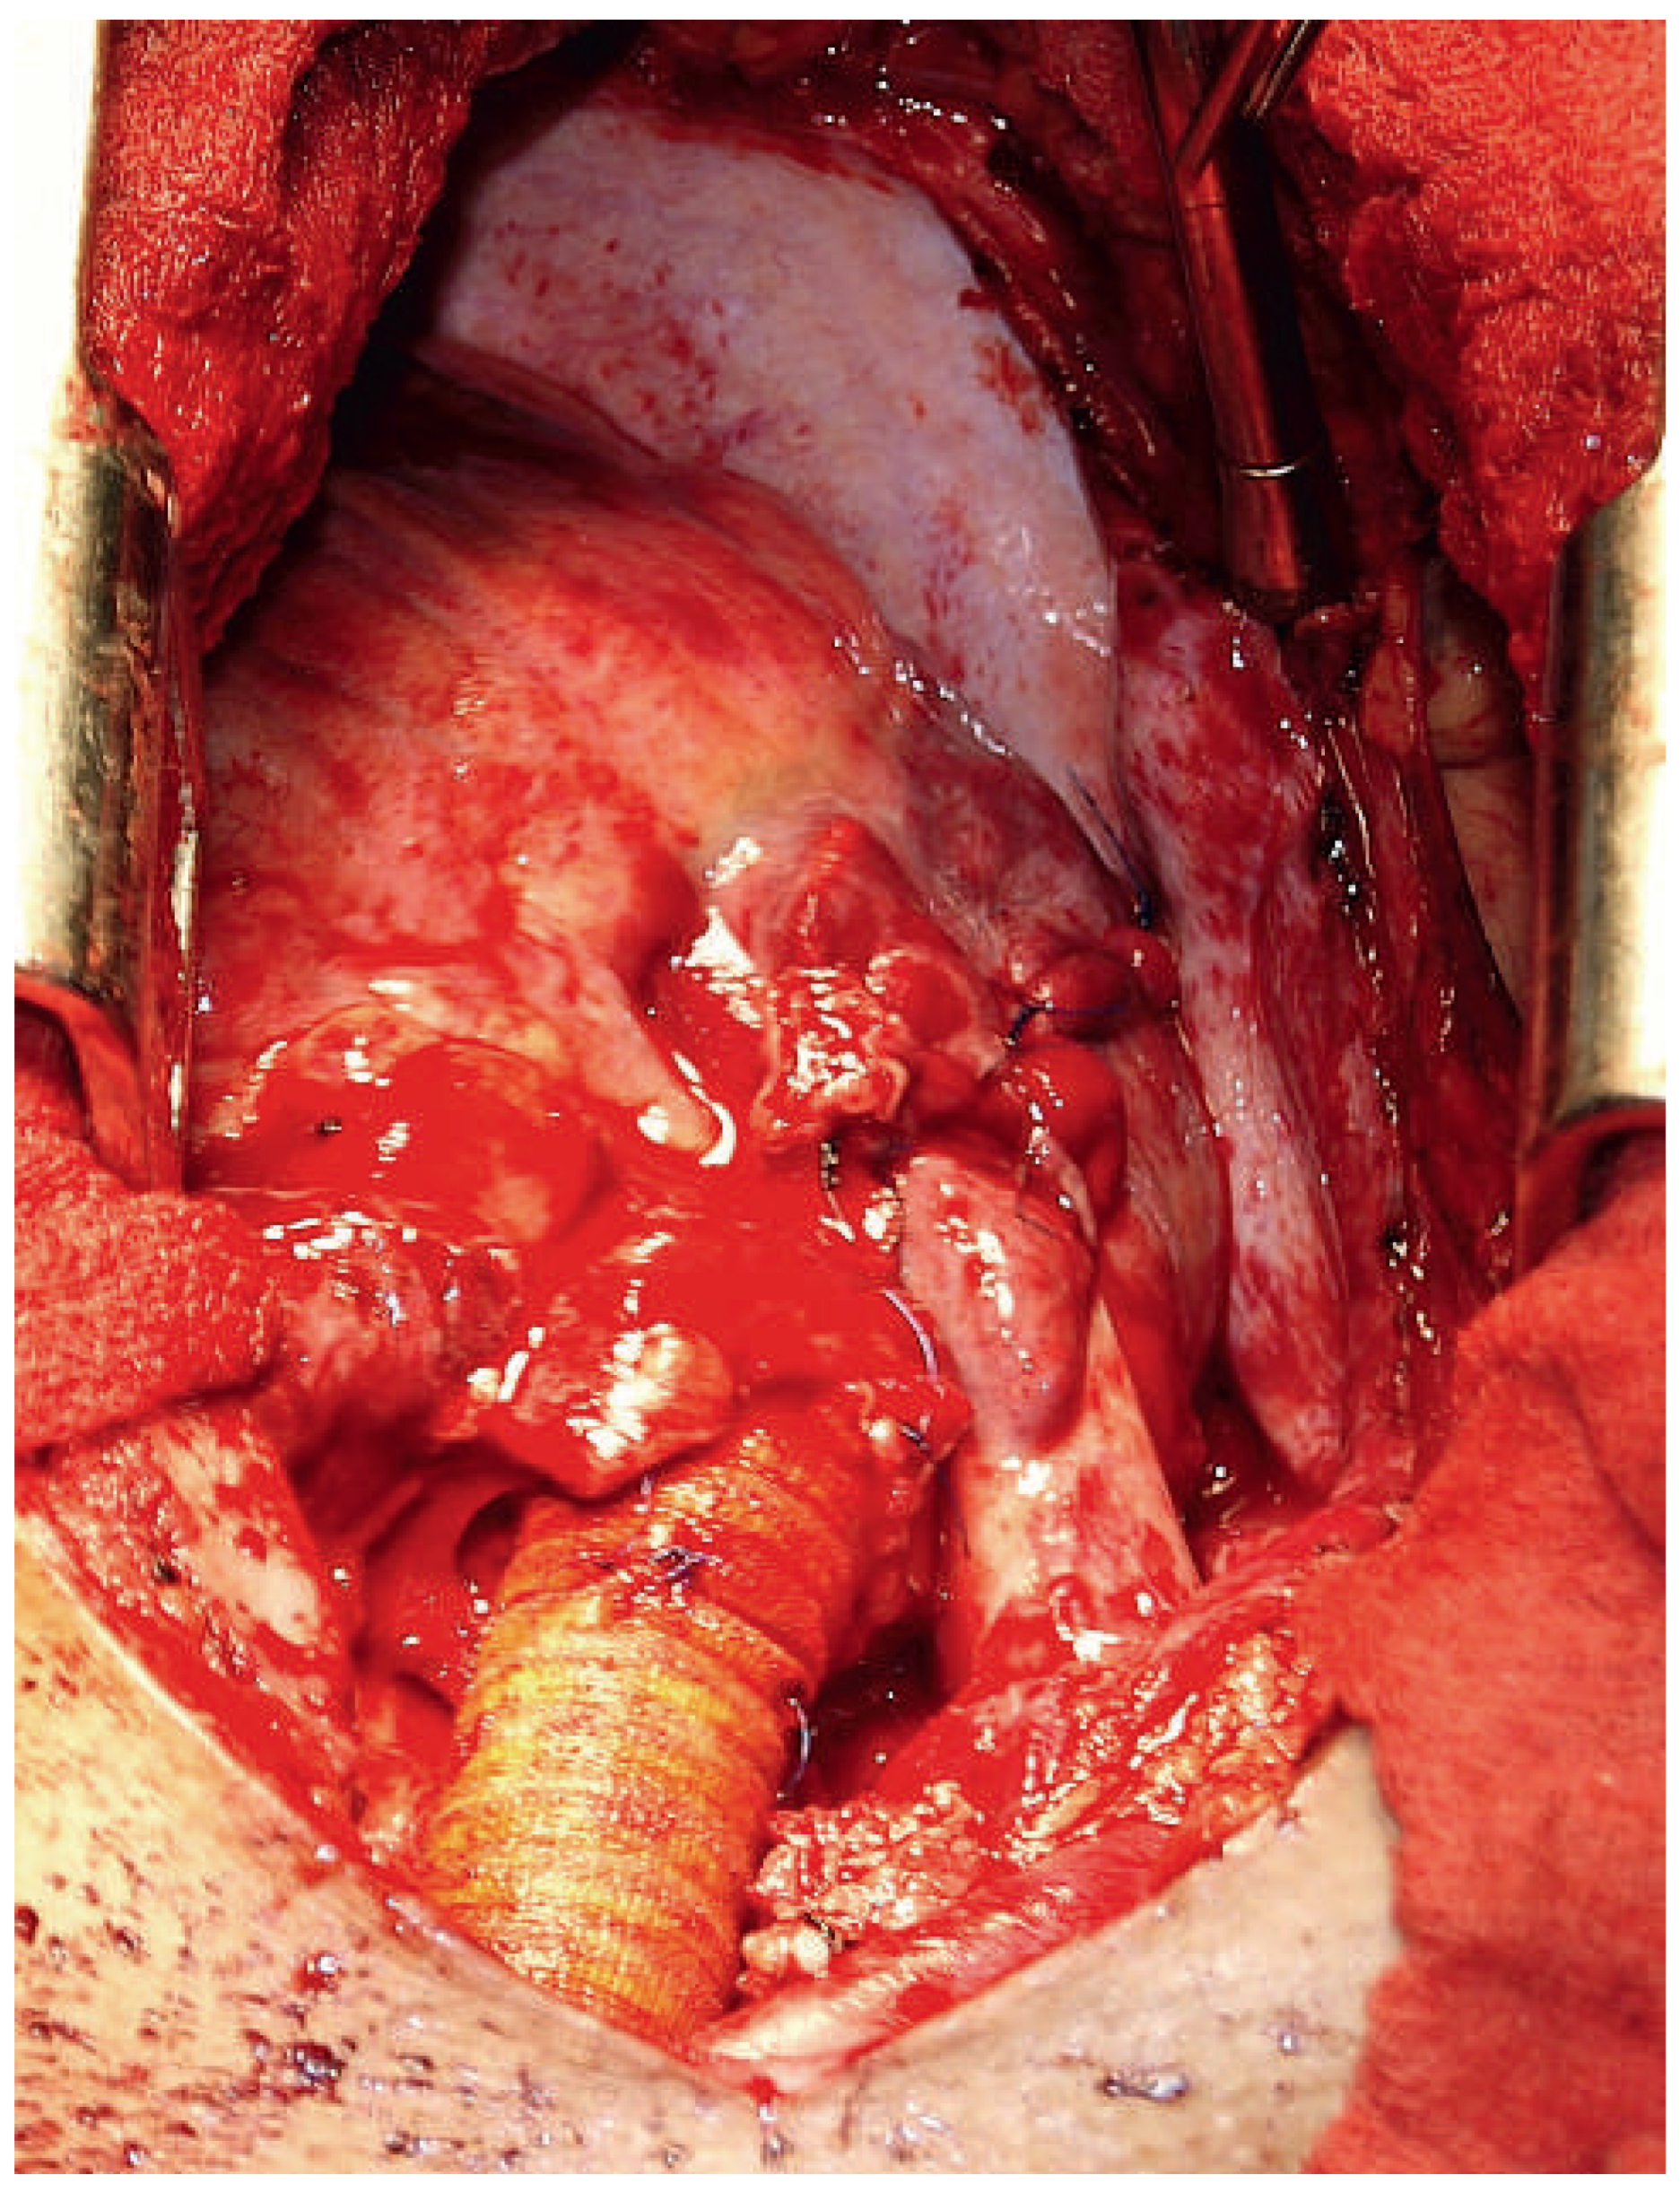

At Yangon Medical University, clinical and echocardiographic findings were confirmed. In addition, chest X-ray revealed a cardiothoracic ratio at its upper limit, but was otherwise found to be normal (Figure 1). Diuretic therapy was introduced and the patient temporarily improved.

Figure 1. First chest X-ray without any evidence of a major thoracic aortic injury.